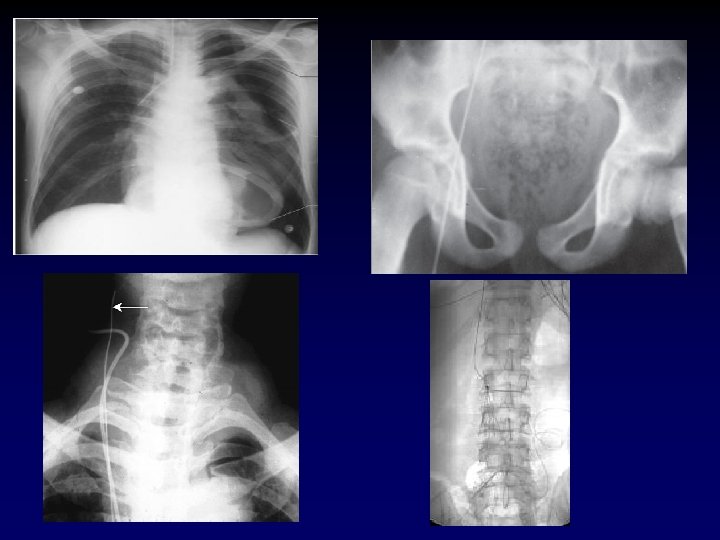

Tube Thoracostomy • Indications: − Hemothorax/Pleural effusion − Pneumothorax − Note for tension pneumothorax first tx should be 14 or 16 guage angiocath in 2 nd intercostal space in midclavicular line. • Anatomy: • 5 th intercostal space in the anterior axillary line (at the level of the nipple). • Measure tube from insertion site to apex of lung.

Tube Thoracostomy • What you need. . . – Chest tube – Pleurevac – Sterile drapes, gloves and gown – Instruments – scalpel and kelly clamp – Heavy silk suture – Gauze and silk tape for dressing

Tube Thoracostomy • Procedure: − Prep and drape hemithorax − Infiltrate skin, subcutaneous tissue and pleura with 1% lidocaine – – 1. 5 -2 cm incision directly over the 6 th rib down to the rib With a blunt clamp, dissect over the superior edge of the rib. Bluntly pierce the pleura with the clamp and spread the track. Be prepared for a rush of blood, fluid and/or air.

Tube Thoracostomy • Procedure (cont) – Place finger in track to confirm intrapleural positioning and lyse any adhesions. – Insert tube via track (with or without clamp) towards apex of lung. – Attach tube to pleuravac. – Secure tube to patient with heavy silk suture and tape all conections.

Warning! • History of chest tubes, thoracotomies or inflammatory pulmonary pathology. – Assume adhesions between the lung and the chest wall. – The chest tube insertion cause a lung laceration. • Be very careful how low you are, you can easily place an abdominal tube if you are not careful.